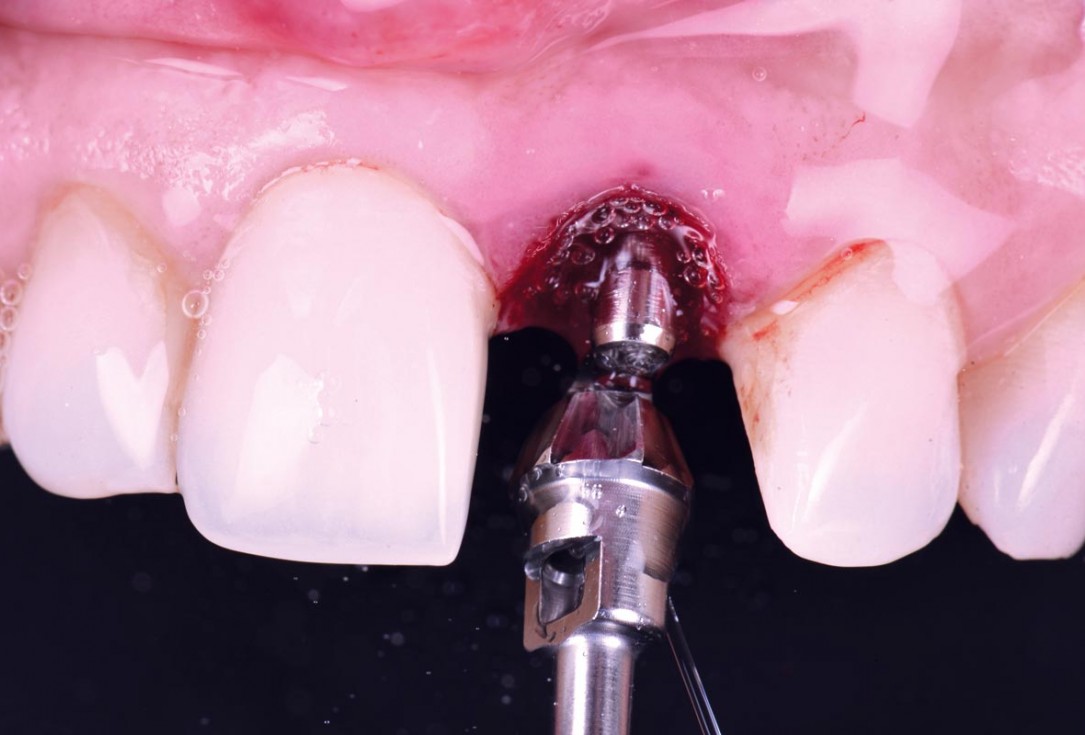

11/30 - Bone profiler was used to remove supracrestal boneExcellent aesthetic result of buccal augmentation with mucoderm® and maxgraft® after immediate implant placement - 3-years follow-up - Dr. A. Puišys